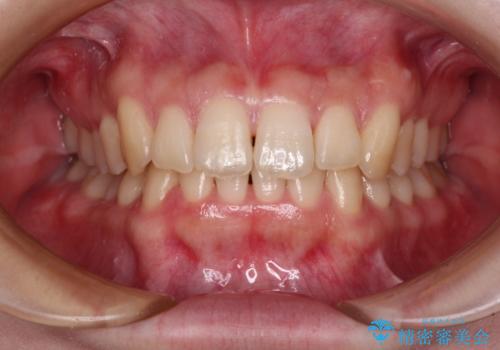

奥歯の咬み合わせを改善しながら、並行してインビザラインで歯列を整えることとしました。

カリエールディスタライザーやワイヤー矯正を併用したことで、確実かつ短期間で治療を終えることができました。